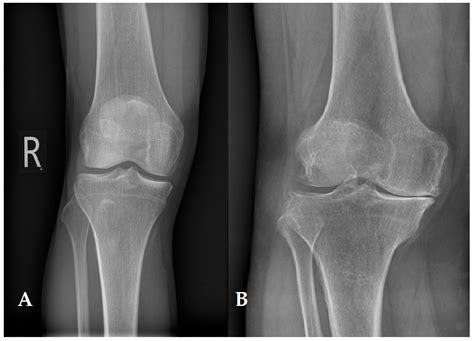

Detailed view of human knee anatomy

The cartilage found in the knee is primarily articular cartilage, a type of hyaline cartilage that covers the ends of the bones. Unlike other tissues in the body, it has a unique composition that allows it to withstand significant compressive forces. It consists of a dense network of collagen fibers and proteoglycans, which attract water to create a gel-like consistency.

Because knee joint cartilage is avascular—meaning it lacks a direct blood supply—it relies on synovial fluid to obtain nutrients and remove waste products. This process, known as imbibition, occurs during the compression and release cycles of movement, which is why consistent, low-impact exercise is essential for its health.